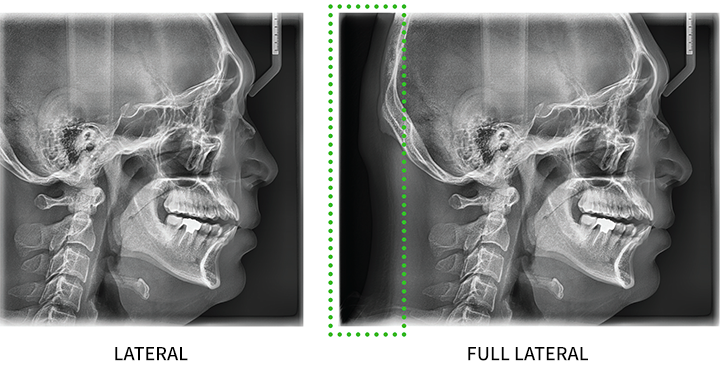

Il tipo di scansione cefalometrica offre due dimensioni di immagine: LAT e FULL LAT, permettendo agli utenti di selezionare quella più adatta alle proprie esigenze diagnostiche. La modalità FULL LAT fornisce immagini specializzate di alta qualità che coprono l’intera area laterale, offrendo un aumento del 30% nelle dimensioni rispetto alla modalità LAT. Questo permette una diagnosi più completa nelle aree cruciali per l’ortodonzia, come l’occipite e la regione maxillofacciale, risultando particolarmente vantaggioso per la pianificazione di interventi ortodontici e chirurgici.